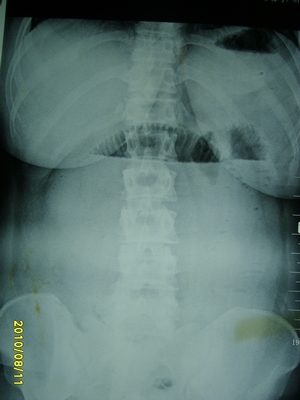

5天前突发腹痛剧烈难忍,伴解淡血水样便。近一天来腹痛缓解,没有明显的腹膜炎的体征。今天照的腹部ct。从ct上看感觉是一个绞窄性肠梗阻,但是现在没有腹痛。不好解释

请放射科的专家,帮帮看看。从影像学的角度来看看。这是不是一个绞窄性肠梗阻。

高位肠梗阻(不全性),原因小肠(空肠)扭转,肠壁水肿增厚,成年人肠梗阻要排除合并占位,建议手术。

绞窄性肠梗阻_肠管套叠 扭转,肠壁明显水肿。

支持绞窄性肠梗阻,肠壁明显水肿并见有多发小泡状积气--肠坏死